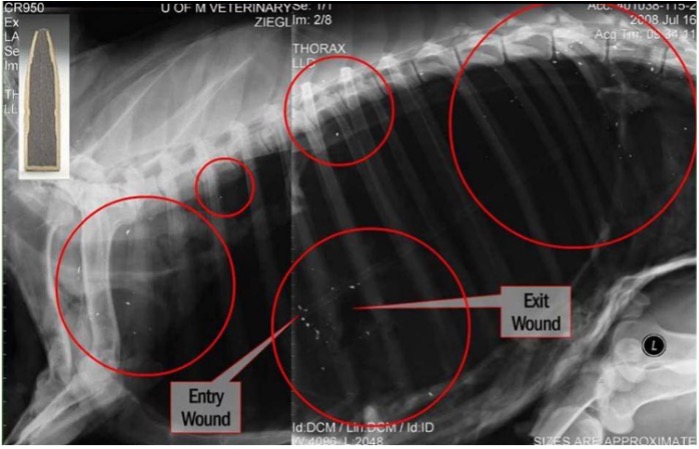

Lead fragments not visible to the naked eye have been found as far as 18 inches from the wound channel. Photo Credit/Description: X-ray of a domestic sheep shot with lead ammunition. Bullet fragments are visible as bright specks within the red circles and are located throughout the thoracic cavity and into the pelvic cavity. Photo courtesy of Minnesota Department of Natural Resources, Farmland Wildlife Populations and Research Group, 35365 800th Ave, Madelia, MN 56062.

After years of development, today's copper bullets are available in a large array of calibers, weights, and designs that meet or exceed the performance of their lead counterparts. While some lead bullets can lose up to 40% of their mass on impact, spraying into tiny fragments up to 18 inches from the wound channel, copper bullets typically retain 95 to 100% of their mass, which can improve bullet penetration with a similar wound channel.